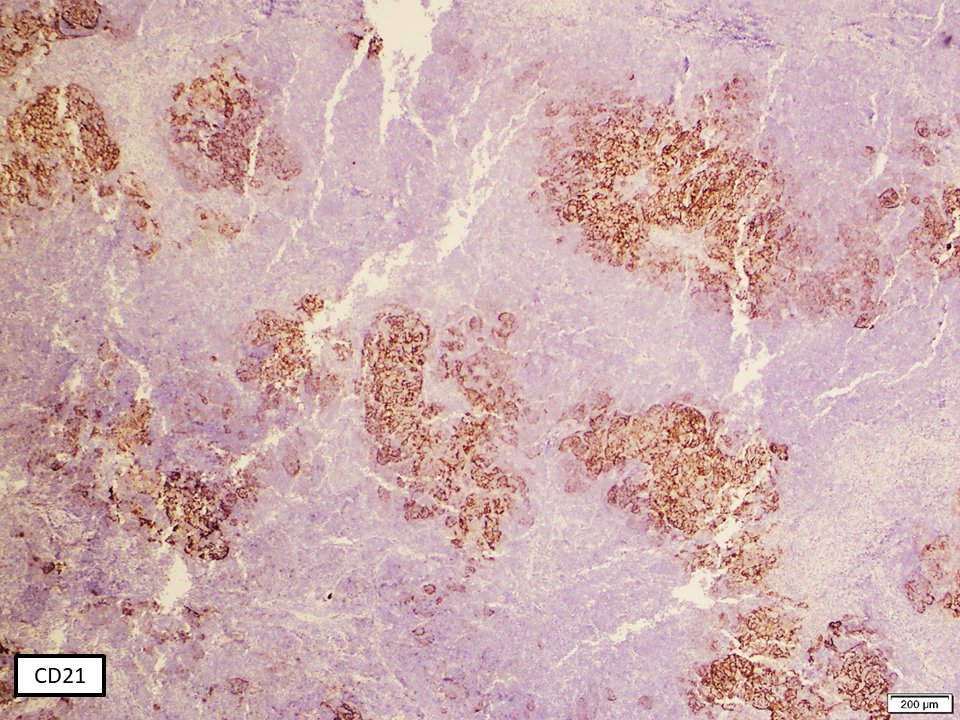

(2/3) CD21 stain highlights expanded and disrupted follicles by large cell lymphoma. Ki67 is remarkably high in the large cell transformation area, in comparison to background low grade FL #hemepath #LJMFridayUnknowns #VirtualHemepathMDA #lymsm #endcancer